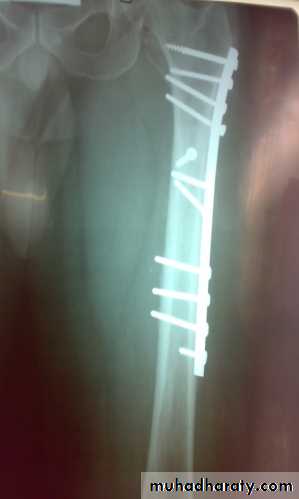

Definitive treatment

closed fractures: by Open reduction and internal fixation, this will decrease the systemic complications.

Fixation of femoral shaft fracture